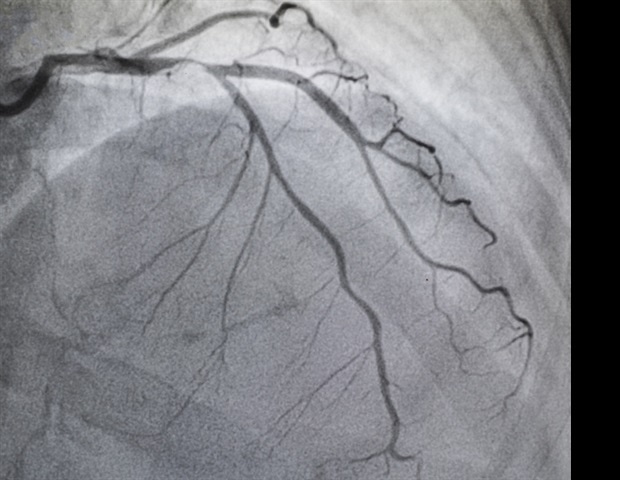

Η στένωση αορτής είναι μια συχνή και προοδευτική πάθηση που εκδηλώνεται ως ασθένεια της καρδιοαγγειακής διαδρομής. Αν δεν θεραπευτεί, μπορεί να προκαλέσει θάνατο εντός δύο ετών σε περίπου το 50% των ασθενών με σοβαρά συμπτώματα. Επειδή τα συμπτώματα της AS, όπως η κόπωση και η δύσπνοια, συχνά συγχέονται με τη φυσιολογική διαδικασία γήρανσης, η έγκαιρη διάγνωση είναι κρίσιμη για να παραπεμφθούν οι ασθενείς για θεραπεία και να περιοριστεί η πρόοδος της νόσου.

Όπως έγινε γνωστό, οι ηλικιωμένοι Αφροαμερικανοί διατρέχουν υψηλότερο κίνδυνο θνησιμότητας λόγω της AS, παρά τις χαμηλότερες διαγνωστικές τους πιθανότητες. Αυτό αναδεικνύει την ανάγκη ενίσχυσης της παρακολούθησης στον συγκεκριμένο πληθυσμό. Η μελέτη Recognition & Evaluation of Aortic Stenosis to Create Health (REACH) πραγματοποίησε μια προοπτική έρευνα, όπου διαχωρίστηκαν οι συμμετέχοντες σε δύο ομάδες: μια με μέτρια έως σοβαρή AS και μια χωρίς, επιβεβαιωμένες μέσω ηχοκαρδιογραφήματος.

Η έρευνα περιλάμβανε συνολικά 346 ασθενείς, εκ των οποίων το 47.1% ήταν άνδρες και το 26.9% Αφροαμερικανοί. Ο αλγόριθμος ASI αποδείχθηκε ότι ανίχνευσε σωστά το 90.5% των περιπτώσεων μέτριας έως σοβαρής AS στον γενικό πληθυσμό και 100% στις Αφροαμερικανές. Η ειδικότητα του αλγορίθμου υποδείκνυε ότι ανίχνευσε το 70.9% των υγιών ατόμων, επιβεβαιώνοντας την αξία της μεθόδου για τη διαλογή ασθενών.